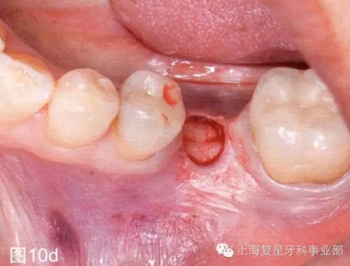

第二天患者就診進(jìn)行手術(shù)。用0.12%葡萄糖酸氯已定漱口水(Oralgene,Laboratorios Maver)含漱2分鐘后,進(jìn)行消毒和術(shù)區(qū)的準(zhǔn)備,在缺牙區(qū)(36#牙區(qū)域)的頰舌側(cè)和頂部進(jìn)行局部麻醉(2%鹽酸利多卡因和1:100000腎上腺素)。幾分鐘后,置入外科導(dǎo)板,在外科導(dǎo)板上的孔洞中置入中空的圓柱形金屬引導(dǎo)管,然后引導(dǎo)軟組織打孔器進(jìn)入,其轉(zhuǎn)速為1200rpm。然后去除引導(dǎo)板,用剝離子去除截面的軟組織,并浸泡在鹽溶液中(圖10b-d)。

圖10d:去除剝離的軟組織